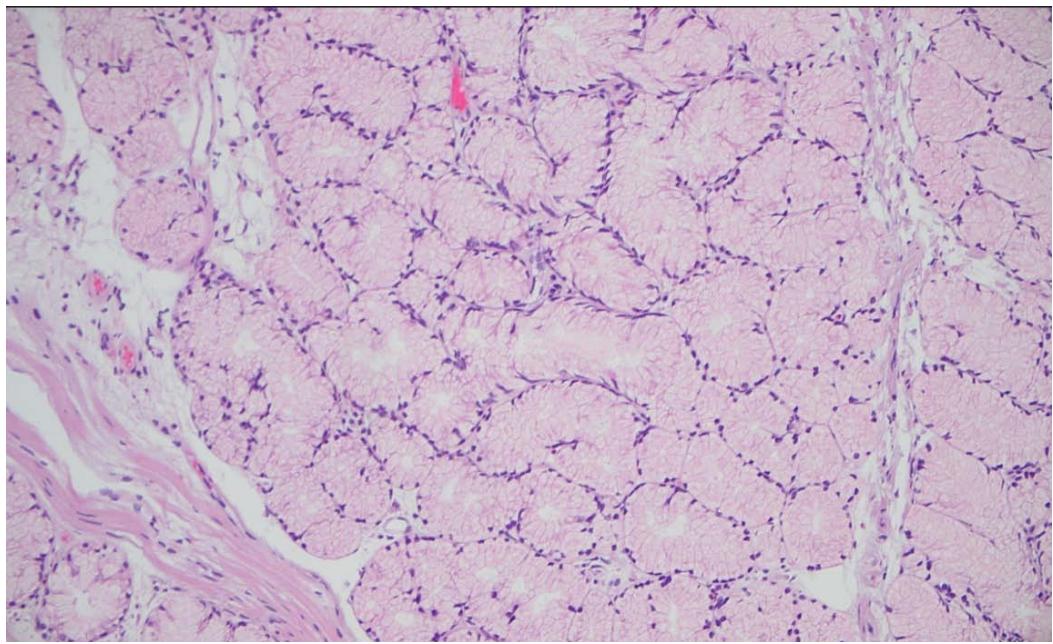

A 64-year-old male with history of heart failure with reduced ejection fraction, chronic renal failure stage 5, coronary artery disease, diabetes mellitus, hypertension, stroke, benign prostatic hyperplasia and tobacco use disorder, presented to the hospital for a nephrology follow up visit. Detection of combined iron deficiency and chronic disease anemia (decreased hemoglobin $6.6\mathrm{g / dl}$, hematocrit $20.6\%$ and iron 34 ug/dL; with normal MCV 91.7 fL, and ferritin 69 ng/ml) prompted upper endoscopy and colonoscopy. The upper endoscopy showed a $1.5\mathrm{cm}$, pink-tan polyp in the duodenum, which was resected. The histopathological examination revealed BGA/BGH type 3 without dysplasia or malignancy (Figure 1 & 2). Immunohistochemistry revealed intact expression of DNA mismatch repair proteins (MLH1, MSH2, MSH6 and PMS2) supporting lack of microsatellite instability. Due to the rarity of the lesion next generation sequencing (Oncomine Focus, ThermoFisher) was performed on extracted DNA revealing a KRAS G12D genetic alteration. In addition, the colonoscopy revealed three tubular adenomas (one $0.4\mathrm{cm}$ pedunculated polyp in the ascending colon and two sessile polyps ranging from 0.3 to $0.5\mathrm{cm}$ in the transverse colon). Of note, the patient died three months later due to respiratory failure from SARS-CoV-2 infection.

Figure 2: Photomicrograph of Brunner gland nodule (H & E x200)